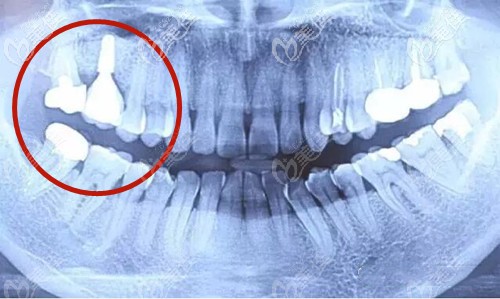

鄭州金水春芽口腔門診部

人氣 0.2 活躍 6.8 診療科目 口腔科 //醫(yī)學影像科 | X線診斷專業(yè)(限口腔)******